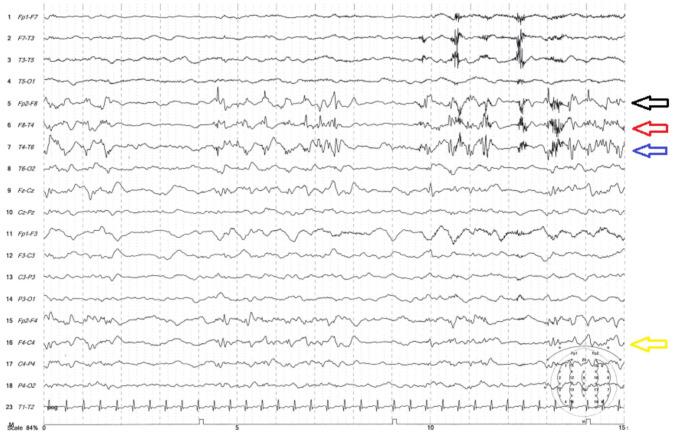

We describe the clinical manifestation and disease course of the first diagnosed case of anti-AMPA receptor encephalitis at the Neurology Department of Children's Hospital 2 in November 2020. A previously healthy 10-year-old presented with symptoms over 2 periods. During each period, the patient presented with multiple focal seizures, a cognitive-behavioral disorder, and amnesia. The brain magnetic resonance imaging (MRI) results were persistently normal. Electroencephalography (EEG) recorded many focal spikes and spike waves. Antibodies against N-methyl D-aspartate (NMDA) were not detected. Antibodies against AMPA receptors were detected in the serum and cerebrospinal fluid using an indirect fluorescent antibody test. This patient was treated with immunotherapy, including methylprednisolone and intravenous immunoglobulin (IVIG), and antiepileptic drugs, such as oxcarbazepine, topiramate, and levetiracetam. The seizures were controlled, but the cognitive-behavioral disorder was only partially resolved.

我们描述了2020年11月在儿童医院2神经内科首次诊断的抗AMPA受体脑炎病例的临床表现和病程。一名此前健康的10岁儿童在两个阶段出现症状。在每个阶段,患者均出现多次局灶性癫痫发作、认知行为障碍和失忆。脑磁共振成像(MRI)结果一直正常。脑电图(EEG)记录到许多局灶性尖波和棘波。未检测到抗N-甲基-D-天冬氨酸(NMDA)抗体。使用间接荧光抗体试验在血清和脑脊液中检测到抗AMPA受体抗体。该患者接受了免疫治疗,包括甲泼尼龙和静脉注射免疫球蛋白(IVIG),以及抗癫痫药物,如奥卡西平、托吡酯和左乙拉西坦。癫痫发作得到控制,但认知行为障碍仅部分得到缓解。